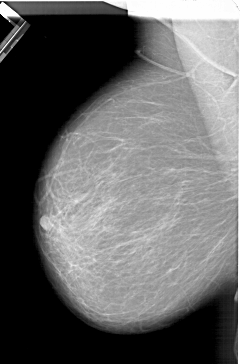

A_1333_1.LEFT_CC

LEFT_CC LINES 6391 PIXELS_PER_LINE 4321 BITS_PER_PIXEL 12 RESOLUTION 43.5 NON_OVERLAY